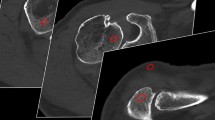

Sensitivities, specificities, PPV, NPV and accuracies for the consensus data on different joint pathologies in FPCT 5-s and 20-s acquisitions are presented in Table 3 and illustrated in Fig. 3.

Fifty-year-old female patient after left antero-inferior shoulder luxation. A marked Hill-Sachs defect of the left humeral head (arrow) can be appreciated already on fluoroscopy (c) performed in a C-arm flat panel CT (FPCT) unit, in coronal FPCT 20-s images (b) and coronal proton-density weighted fat-saturated (PDw FS) MR-arthrography images (e). Adjacent articular sided partial tear of the supraspinate tendon was only seen on MR due to lack of intra-articular contrast in FPCT at this location (cranially adjacent to arrow in b and e, false-negative finding). Corresponding Bankart-lesion of the antero-inferior labrum can be nicely delineated on both FPCT and axial PDw FS images (in a and d; true-positive finding). Bursal effusion/hematoma is seen on coronal PDw FS and T1-weighted fat saturated (T1w FS) images of MR-arthrography (arrowheads in e and f) but without extra-articular contrast leakage indicative of transmural rotator cuff tear. Asterisks in b, e and f mark small intra-articular coagulum, nicely depicted in both modalities

Differences between FPCT 5-s and 20-s acquisitions seen in the quantitative measures are moderately reflected in the qualitative ratings. A slight increase in sensitivity for labrum or biceps tendon pathology (40 % vs. 50 %) and a marked increase for cartilage and rotator cuff pathologies (40 % vs. 75 % and 20 % vs. 73 %, respectively) were noted for FPCT 20-s vs. 5-s acquisitions. Although the FPCT 20-s acquisitions delivered better image quality with fewer artifacts, the diagnostic performance for the remainder of joint pathologies with regard to specificity, PPV, NPV and accuracy was comparable to FPCT 5-s acquisition. This corroborates findings of recent studies with excellent image quality for bone visualization using cone-beam CT [26] and good diagnostic performance for cartilage lesions in FPCT using an 8-s intermediate radiation dose protocol [9]. In contrast to published studies on the performance of MDCT arthrography for cartilage and labrum defects of the shoulder [27–31], sensitivity of FPCT was low. Although generally higher in 20-s acquisitions sensitivities for both pathologies amounted to only 75 % and 50 %, well below reported values in MDCT arthrography. A major source for deterioration of image quality are different attenuation profiles and incomplete trajectories of the volume of interests of a 200 ° C-arm rotation around the shoulder joint which can lead to marked truncation artefacts. In addition, as seen in our FPCT arthrograms, potential high spatial resolution of FPCT can be hampered by susceptibility to cone-beam and ring artifacts, decreasing sensitivity for e.g. cartilage and labrum defects. MDCT arthrography of the shoulder is less affected by beam hardening artifacts, although photon starvation in analogy to FPCT is an issue [32]. Additional artifacts may occur when using cone-beam instead of fan-beam geometry [5, 6, 33]. Patients with metallic implants were therefore excluded from this study as this was beyond the scope of this study.